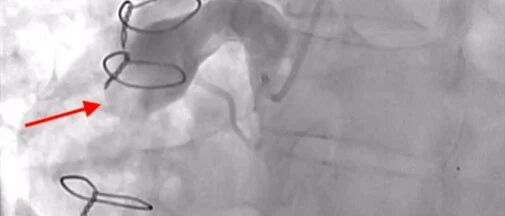

病例 | 中年男性胸痛+肌钙蛋白升高+造影无斑块,竟是多支SCAD!男性中罕见,你会如何追问病因? 心在线 · 公众号 · · 3 月前 · |